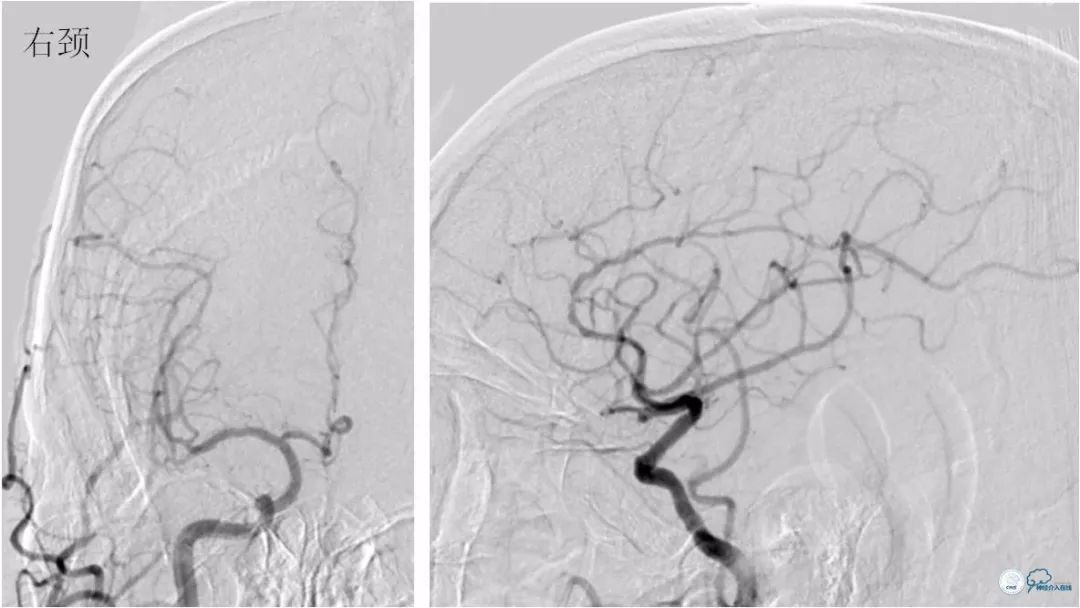

DSA:左椎动脉优势,左椎动脉V1段重度狭窄,右椎动脉V1段中度狭窄,双椎动脉V4-基底动脉下段重度狭窄,狭窄率约为85%,狭窄段有AICA发出,双侧后交通动脉未开放(图6-9)。

图6

图7

图8

图9